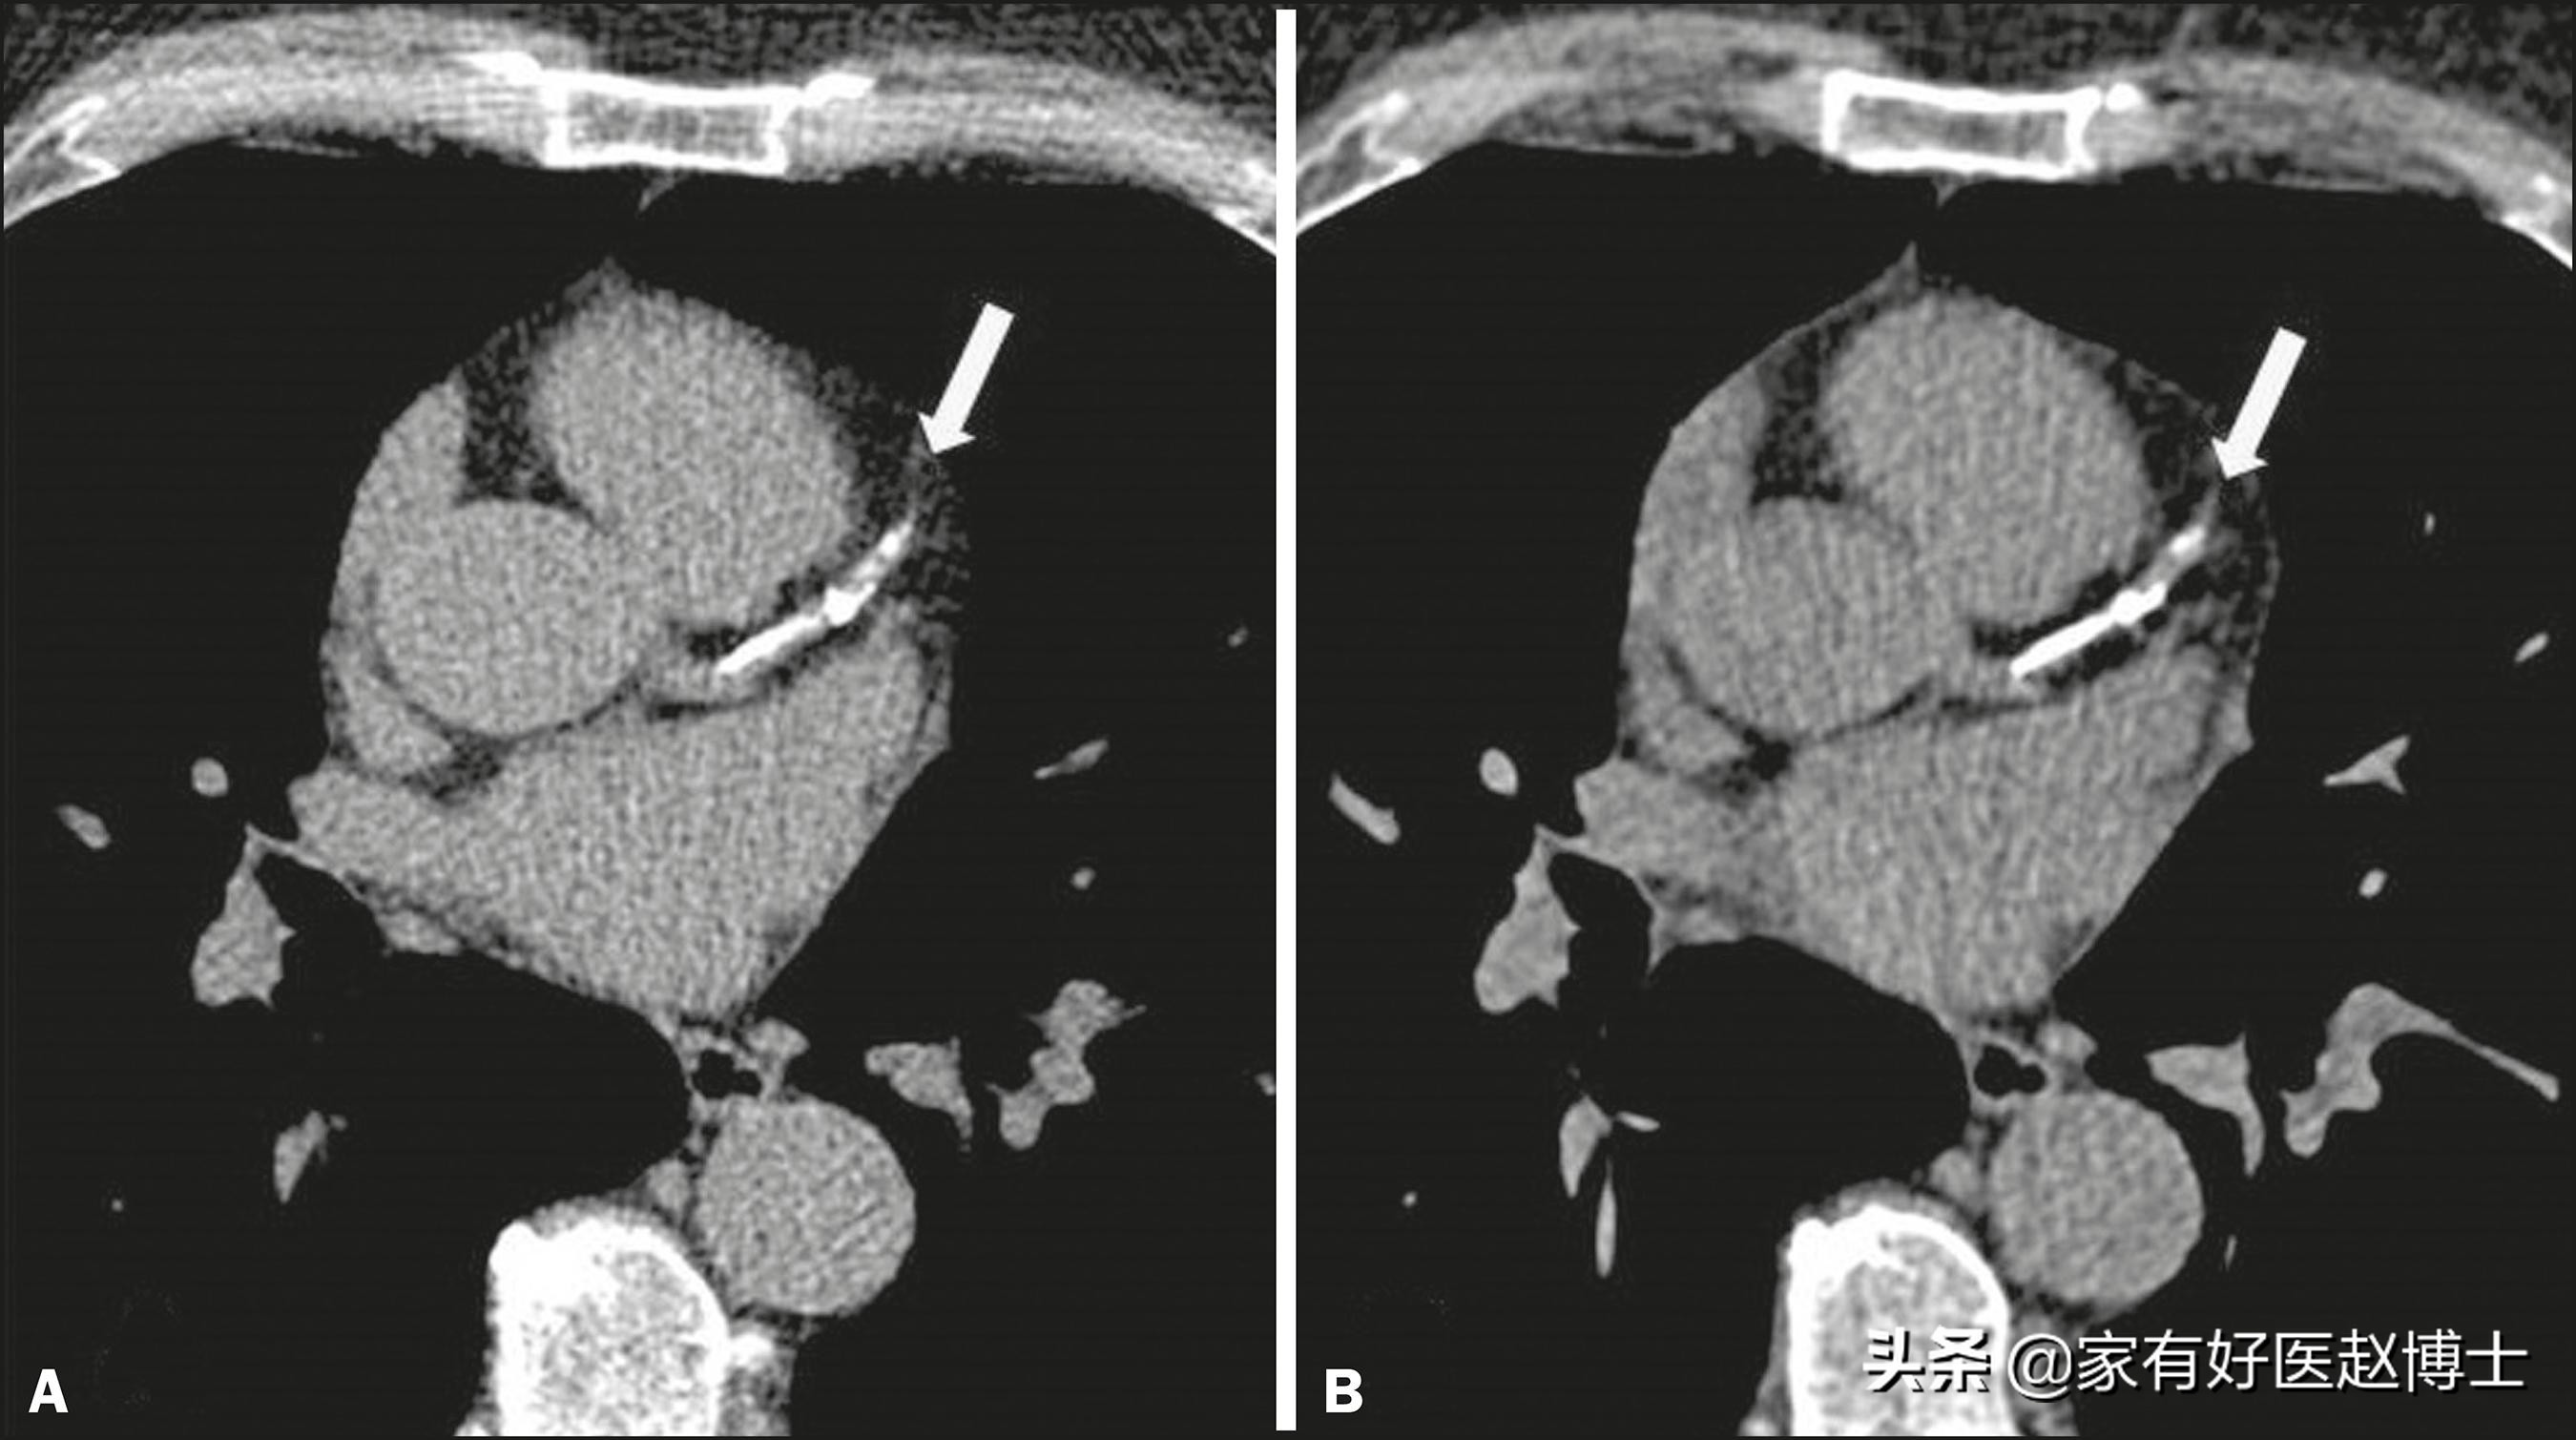

前面我们说到的,主要是一些重要器官当中出现的钙化,而还有一类钙化也在体检中常常遇到,这就是血管的钙化。有时候,肺部CT扫描可以看到主动脉或冠状动脉上的钙化,而颈动脉超声检查则可以识别出颈动脉内膜中的钙化。

动脉钙化与器官中的钙化不同,它并不会提示癌症风险,但是,它却常常意味着另一项足以致命的危险,这就是动脉硬化。大家需要记住很重要的一点,这就是:存在动脉钙化就等于存在动脉硬化。

因此,如果在体检中发现了动脉钙化,请仔细回顾一下:自己的血压、血糖、血脂等重要心血管指标是否都正常,如果存在异常,那应该尽早开始进行干预和治疗;哪怕这些指标都正常,那说明年龄和衰老这项单一因素已经造成了心血管系统的退化,要充分意识到自己正在面临不断增大的心血管风险。